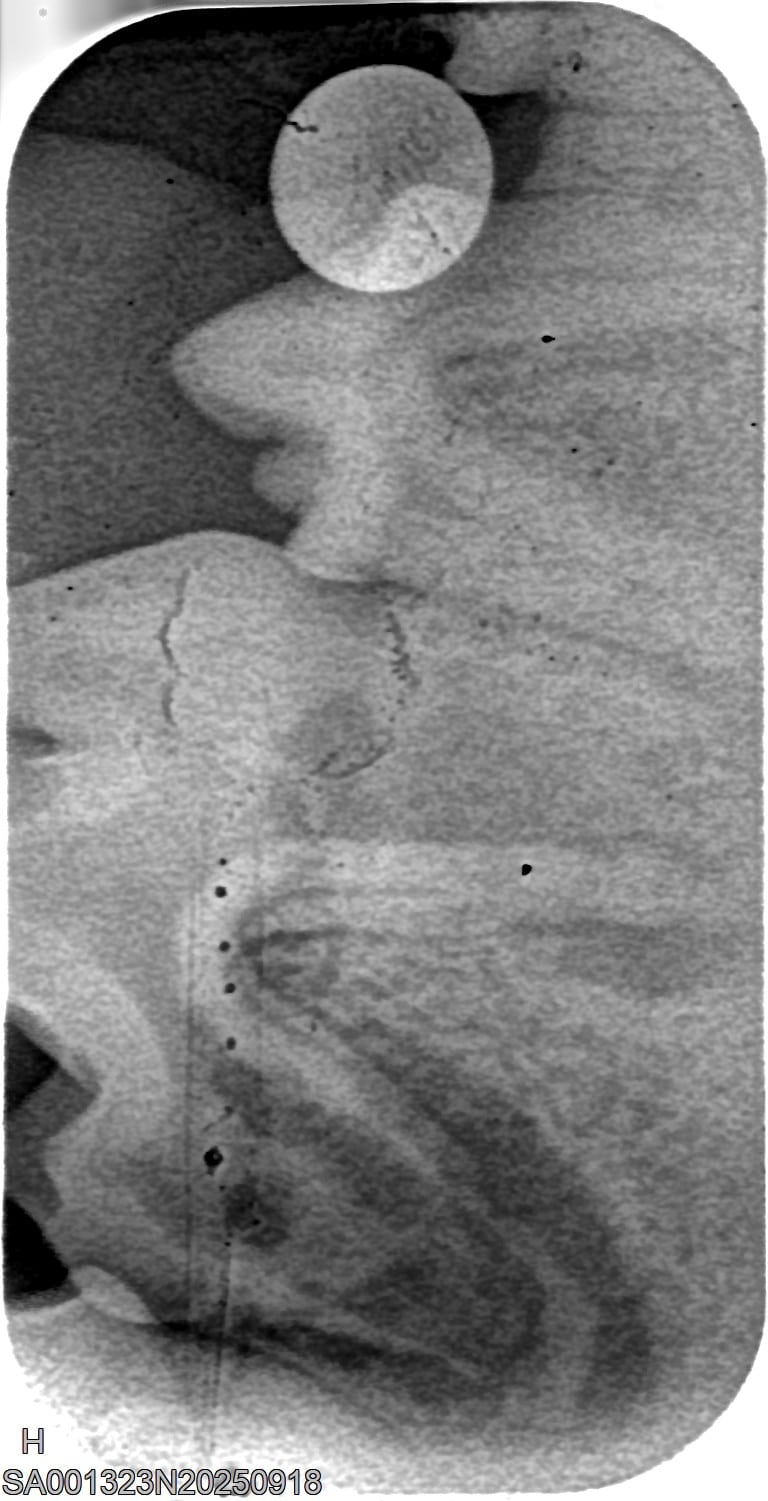

Um das Ausmaß von Zahnstein und möglichen Folgeschäden richtig zu beurteilen, ist eine tierzahnärztliche Untersuchung erforderlich. Neben der Sichtkontrolle werden häufig Röntgenaufnahmen der Zähne angefertigt, um Entzündungen oder Veränderungen unter dem Zahnfleisch zu erkennen. So kann der Tierarzt gezielt entscheiden, welche Zähne erhalten werden können und wo eine Behandlung notwendig ist. Eine frühzeitige Diagnostik hilft, Schmerzen zu vermeiden und die Zahngesundheit des Hundes langfristig zu sichern.

Behandlung von Zahnstein beim Hund

Röntgenbilder

(Fraktur + Wurzelentzündung durch Zahnstein)